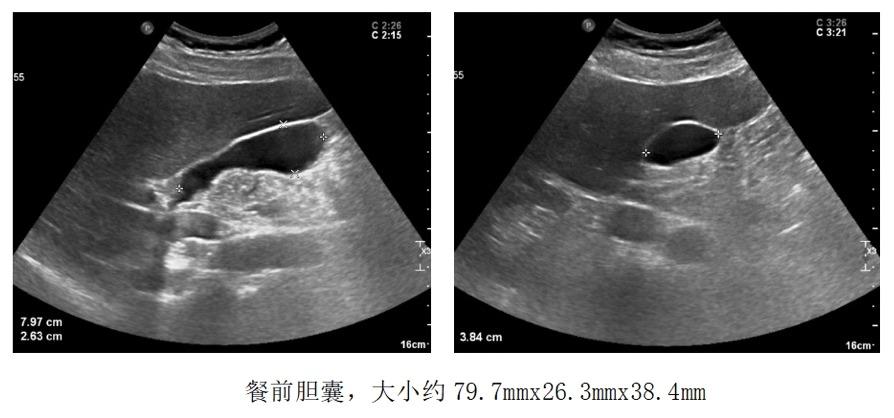

进行胆囊脂餐实验,让患者口服油腻食物,半个小时后再行超声检查,通过前后胆囊的大小变化来判断胆囊的收缩功能。

由此可得,该患者胆囊收缩率约为80%,胆囊收缩功能正常,具有保留胆囊的意义。(一般情况下缩小50%以上,可视为胆囊收缩功能正常)